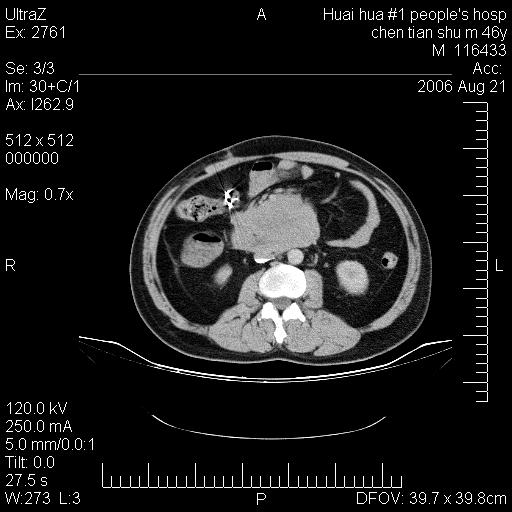

患者,男,46y。腹痛2月,消瘦。

十二指肠水平段占位,考虑间质瘤或平滑肌瘤。

肿块较大,腹膜后占位,境界欠清,周边脂肪密度较高呈条状影,有没有脂肪肉瘤可能,

缺少完整的三期图像。考虑肠系膜脂膜炎mp(肿块型)。

鉴别:间质瘤(这么大而无囊变不可思议)、平滑肌瘤/肉瘤、淋巴瘤、类癌,脂肪类肿瘤、转移瘤等。

十二指肠水平段占位,考虑间质瘤。

首先考虑小肠间质瘤。

十二指肠水平段软组织密度占位,考虑间质瘤可能性大。

腹膜后占位,境界欠清,考虑来源于十二指肠病变,间质瘤或平滑肌肉瘤可能性大。建议活检。

手术病理结果:原发性小肠恶性淋巴瘤(primary gastrointestinal lymphoma,pgil)是原发于胃肠的淋巴网织系统的恶性肿瘤,在结外淋巴瘤中居第一位,该病少见,临床无特异性,诊断困难,术前主要依靠影像学诊断。胃肠道本身具有较丰富的淋巴组织,因而胃肠原发性淋巴瘤是结外淋巴瘤最常见的部位,文献报道约占胃肠道恶性肿瘤的1%~4%,其中胃约占50%~70%,小肠约占35%~70%,结肠约占4%~6%。影像检查在pgil的诊断及分期中有重要的作用,ct是很有价值的检查方法。

胃肠淋巴瘤病理特点:胃肠道原发性淋巴瘤起源于胃肠壁固有层和黏膜下层的淋巴组织即胃肠粘膜相关淋巴组织(malt),多为粘膜相关淋巴瘤。病理上通常为非霍奇金淋巴瘤,且决大多数来源于b淋巴细胞,很少见于霍奇金淋巴瘤。胃肠原发淋巴瘤比胃肠道癌的发病率要低的多,最常见于胃,其病因可能跟幽门螺杆菌感染有关。幽门螺杆菌能引起胃粘膜损害,引起炎性及免疫反应,淋巴细胞聚集并形成滤泡,可影响胃的正常生理功能,导致胃淋巴瘤的发生。单纯性小肠淋巴瘤是常见好发于回盲末端,受累的肠段较长,可单发、多发,甚至累及整个小肠。原发性大肠淋巴瘤罕见,以直肠和盲肠最多见。病变大体观可表现为胃肠腔内外的肿块,也可表现为从黏膜下到浆膜面肠壁的纵向浸润,并且常常伴有肠系膜淋巴结肿大。任何情况下,肿瘤几乎总是导致一定程度的肠壁增厚,可对称或不对称,病变与正常组织间常无明确分界,肠腔可狭窄、正常或动脉瘤样扩张,后者主要是肿瘤在肠壁内浸润,破坏肠壁内植物神经丛所致。以上改变成为ct检测病变的病理基础。

肠道淋巴瘤的ct表现分为4类

1) 壁内浸润型, (2)多发结节型, (3)肠系膜受累伴腔外肿块型(本型就是),(4)肿块型。